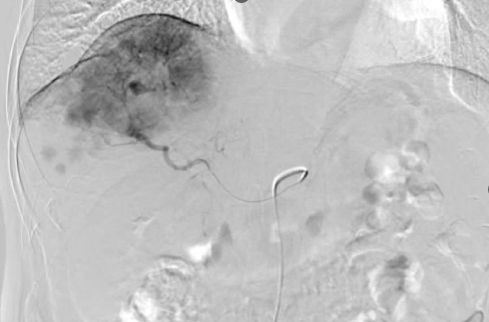

图2行肝动脉置管术

患者入组“肝动脉灌注或静脉输注阿得贝利单抗,联合静脉输注贝伐珠单抗及肝动脉灌注-FOLFOX化疗用于晚期不可切除肝细胞癌(HCC)的一线治疗:一项多中心、开放、随机II期临床试验(HAIbrave-001)”,随机至研究的动脉臂,于2025-01-03至2025-02-14行两程肝动脉造影+肝动脉置管术,术后动脉给予FOLFOX+阿得贝利单抗1200mg,静脉给予贝伐珠单抗800mg